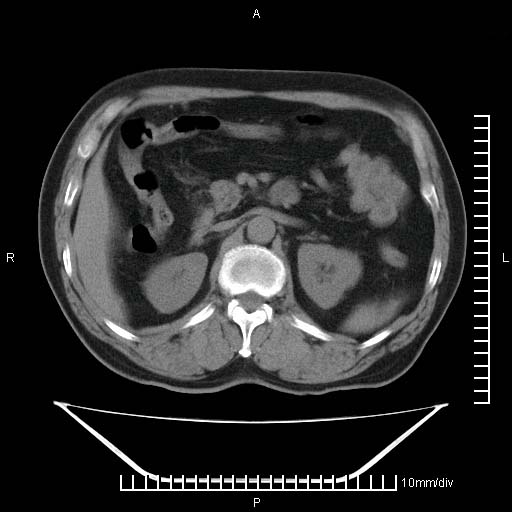

标题: CT25082:肝脏增强:男性,70岁 [打印本页]

标题: CT25082:肝脏增强:男性,70岁

患者以心脏疾病收住院,腹部无明显症状,b超查肝脏有占位。

增强效果不理想。考虑转移,胆囊壁明显增厚,不排除胆囊癌肝转移。

病灶无强化,考虑囊肿。

牛眼征,中心坏死无强化,外缘强化,最外缘又见低密度,考虑转移,与脓肿鉴别

肝内多发转移瘤,右下肺炎症并少量胸水。胃壁增厚建议胃镜,胰尾部“病变”为肠管。

1)肝脏多发性转移瘤(不排除胰尾癌转移所致可能)。2)腹水。3)右侧少量胸腔积液。

增强效果太差了,是手推的吧,不会是团注的,肝内多发低密度灶占位,多考虑为肝ca

ct25082 结果:转移瘤

外院mr结果:胰尾恶性占位。

肝多发低密度灶;轻度强化,较水密度高,考虑转移,不排除肝脓肿